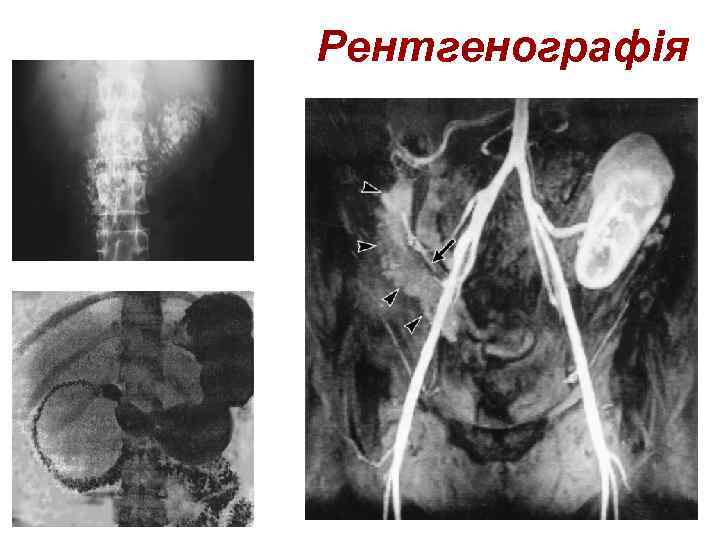

Рентгенографія

Рентгенографія